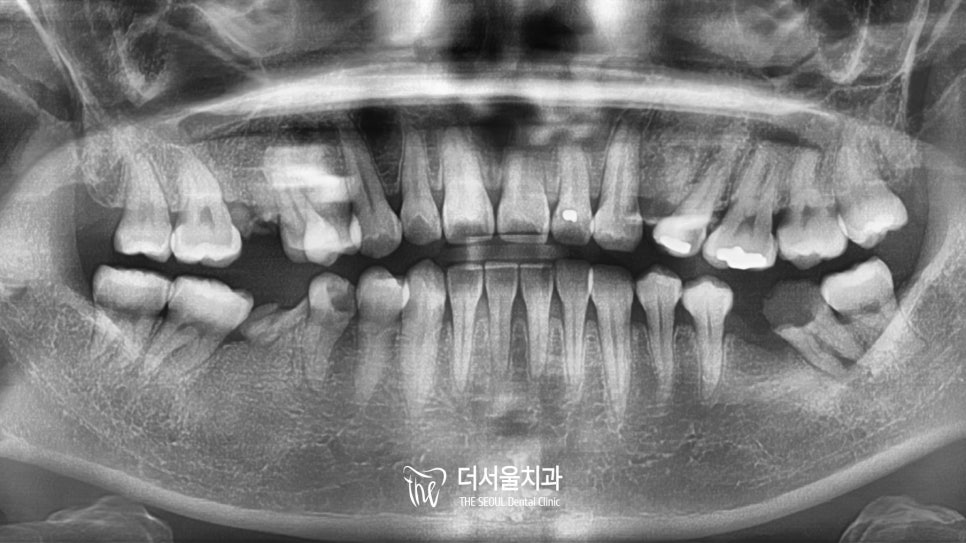

초진 파노라마

일단 이분은 치아가 많이 썩어서

살릴 수 없는 곳들은 발치를 진행하였습니다.

이곳들은 추후 임플란트 식립을 통해

빈 곳을 메꿔주기로 했죠.

다행히 살릴 수 있는 곳들도 있었는데요.

그러나 이곳도 꽤 많은 부분이

감염이 되어 있는 상황이었습니다.

이곳들은 신경치료 및 포스트를 진행하여

살릴 수 있을 때까지 자연치를 살려보기로 했습니다.

위 내용을 환자께 충분히 설명을 드린 뒤

본격적인 과정으로 들어갔습니다.

우선 잔존조직이 남아있지 않도록

깨끗하게 발치를 하였으며,

살릴 수 있는 곳들은 근관치료를 했습니다.